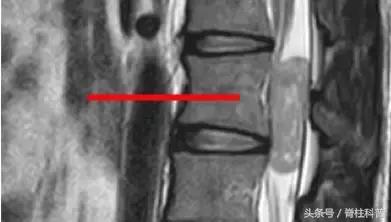

马尾综合症患者资料

脊柱结核

骨质疏松压缩性骨折